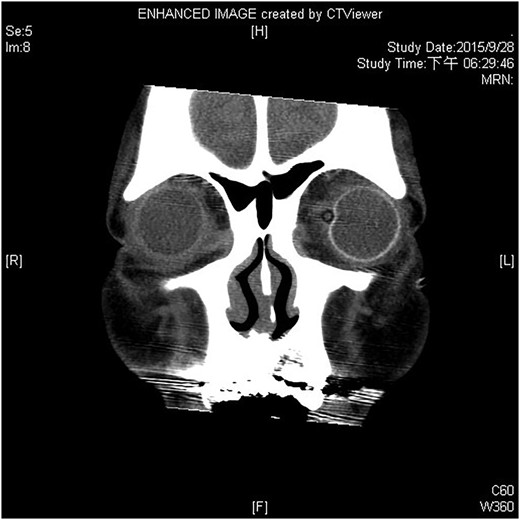

A 60-year-old man was admitted to our medical ward due to aspiration pneumonia. He had a medical history of diabetes mellitus, end-stage renal disease; a tuberculosis bacilli-related thoracic spine infection with paraplegia, and a previous coronary artery bypass graft. During his third day at the hospital, he obtained a ballpoint pen and inserted it into his left eye. On physical examination, the patient appeared to be alert with normal vital signs. The ballpoint pen protruded from his left upper eyelid; it was firmly lodged in his left medial orbit between the globe and nose, causing left eye proptosis (Fig. 1). Neurologic examinations revealed that the patient was neurologically intact except for complete left ophthalmoplegia. Brain CT scanning revealed a tubular foreign body that was located in the anteroposterior plane extending from the orbital apex and directly into the parasellar region (Fig. 2). The metallic portion of the foreign body was entrapped in left optic canal (Fig. 3). There was no evidence of intracranial hemorrhaging or a rupture in the globe (Fig. 4). The patient was treated with high-dose steroids to protect the optic nerve. The plastic ballpoint pen and metallic tip was withdrawn from the orbit smoothly at bedside, and no craniotomy was required. The ballpoint pen had been inserted to an estimated depth of 7 cm through the eyelid and into the orbit. The patient was then transferred to the ICU for close neuro-observation. We initiated intravenous broad-spectrum antimicrobials and vancomycin therapy and continued these medications for three weeks. A psychiatrist was consulted for a complete psychiatric evaluation and suicide prevention. The follow-up CT scan showed no retained foreign bodies or intracranial hemorrhaging (Fig. 5). At the last follow-up examination 2 months after the injury, the patient presented with complete left ophthalmoplegia and blepharoptosis but intact visual function.

The ballpoint pen tip reaches into the parasellar region via the optic canal.